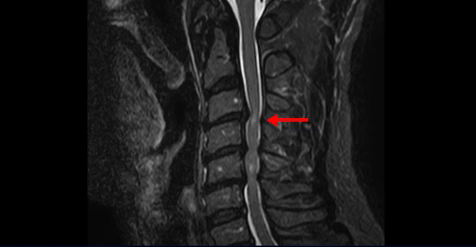

이 환자분은 목디스크 3, 4번의 심한 디스크로 인해 경추척수증이 발생한 환자입니다. MRI에서 보시다시피 심하게 밀려 나온 목 디스크로 인해 척수신경이 눌려서 신경이 손상된 게 하얗게 보입니다.

경추척수증이란 중추신경인 척수가 목디스크나 골화된 후종인대 또는 경추 협착에 의해 심하게 눌려서 손상이 생기는 질환입니다. 이 환자분의 증상은 목이 항상 담 걸린 듯 뻐근하고 걸을 때 발을 헛딛고 젓가락질이 잘 안되며 단추를 끼울 때 잘 안 껴지고 손에 잡은 물건이 자꾸 떨어지려고 하는 상태였습니다. 이는 전형적인 경추척수증의 증상입니다.